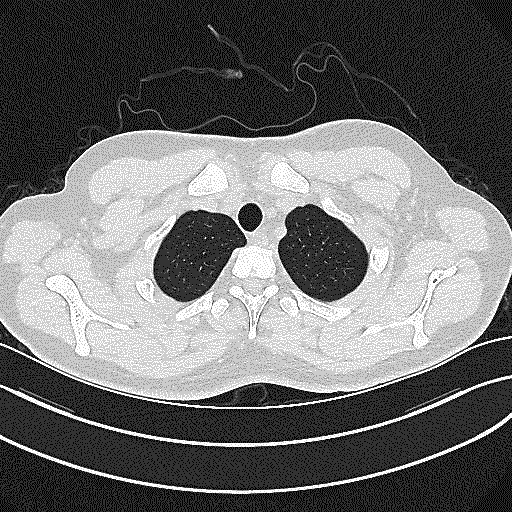

入本院第10天CT.gif